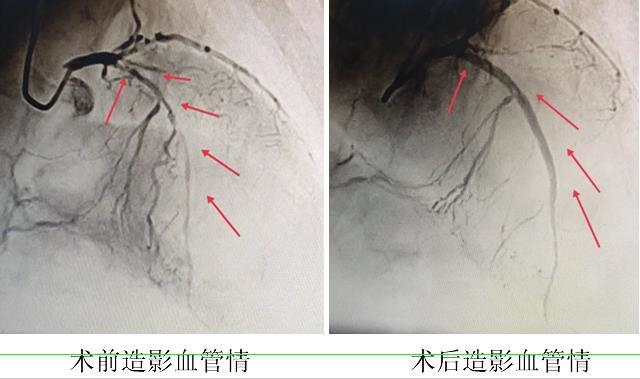

由于患者年龄太大,家属担心介入手术风险,只同意先进行冠脉造影,评估病情,暂时不进行介入手术治疗。13点40分,侯国清及团队为张大爷做了冠脉造影,发现张大爷的右侧冠状动脉几乎完全闭塞,左侧冠状动脉有严重的狭窄。医院充分尊重家属意见,把张大爷转入心血管内科保守治疗,药物治疗两天后,情况没有明显改善,还出现了心衰发作,平躺在病床上都觉得很困难,如果不及时手术,张大爷随时可能出现心肌梗死再次发作、心源性猝死等严重后果。

历时1个小时,侯国清及团队克服重重困难为张大爷成功开通了血管,并植入2枚支架。